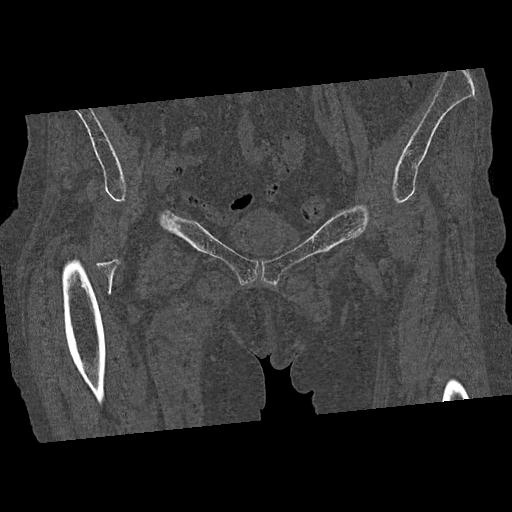

100703 1/27 両股正面+軸 1/29 両股正面+軸 94歳女性 パンソンロン

46666 1/28 両股正面+軸と 1/26 右手関節 2R 76歳女性 右転子部骨折

37 1/18 両股正面+軸 1/22 2R 86歳女性 右転子下

91569 3/25 両股正面とラウエン 70歳女性 人工骨頭+バンクーバー